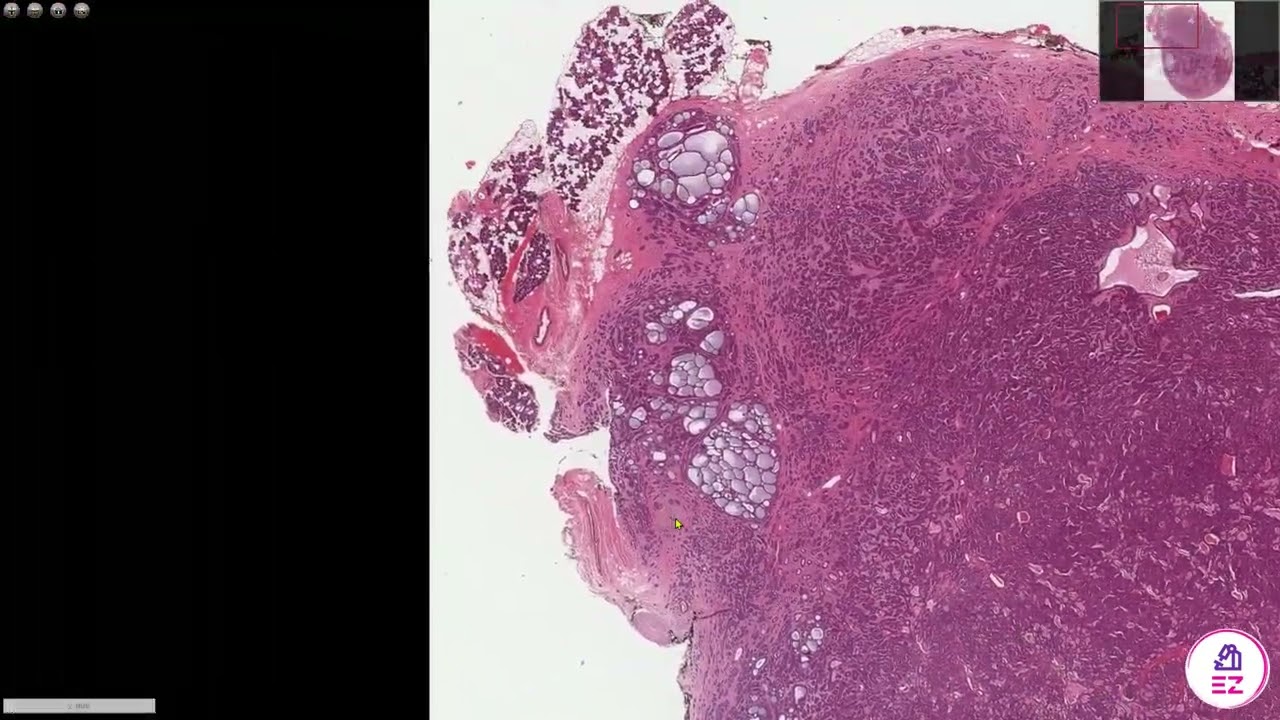

Digital Surgical Pathology 393 Vulva-  Skin adenoid cystic carcinoma

Adenoid cystic carcinoma presenting in the vulva, differential diagnosis discussed with several considerations and examples. Gynecologic Pathology, #DAPA, #DPA, #OUPath #Pathresidents